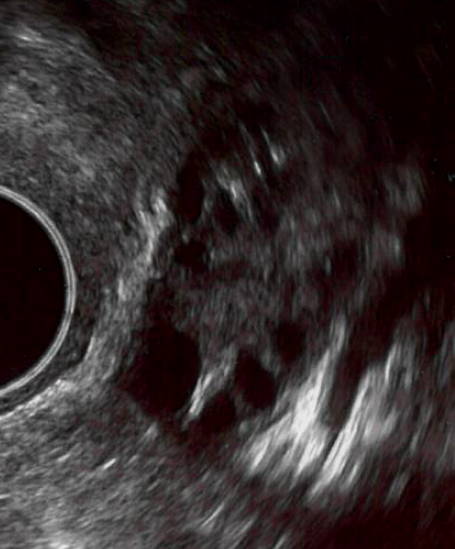

Om de kans op zwangerschap te vergroten, krijgt u medicijnen voorgeschreven die de eierstokken stimuleren. Op die manier komen meestal twee eiblaasjes tot ontwikkeling in plaats van 1 (zoals in de natuurlijke cyclus). Nadat u zich op de eerste dag van de menstruatie heeft aangemeld, heeft u een afspraak gekregen voor een uitgangsecho op de tweede of derde dag van de cyclus. Deze afspraken vinden plaats op het IVF-centrum. Bij een uitgangsecho wordt gekeken of er geen cystes of andere afwijkingen aan de baarmoeder of eierstokken worden gezien die de behandeling kunnen belemmeren. Het is mogelijk dat u wordt gevraagd om bloed te laten afnemen. Hierbij kunnen verscheidene hormonen worden bepaald. Dat kan (indien nodig direct) in het IVF-centrum. Meestal worden er geen bijzonderheden ontdekt en kan de behandeling doorgaan.

In dat geval begint u op cyclusdag 3 met het spuiten van het follikelstimulerend hormoon (FSH: Menopur® of Gonal-F®). De standaard dosering is 75 IE Menopur®. Van deze dosering kan worden afgeweken op basis van leeftijd, eicelvoorraad en/of het resultaat van eerdere stimulaties.

U krijgt een vervolgafspraak na vijf tot tien dagen (afhankelijk van uw cyclusduur of verloop van eerdere stimulaties). Na de tweede controle is het afhankelijk van de groei van het ei-blaasje wanneer en of u nog een keer voor echocontrole moet komen. De controles zullen iedere één tot vier dagen plaats vinden tot dat het ei-blaasje groot genoeg is. Het streven is (een tot) twee ei-blaasjes van 17 tot 18 mm. Bij deze grootte wordt de eisprong kunstmatig in gang gezet door de hCG-injectie (Ovitrelle®). De Ovitrelle® injectie zorgt ervoor dat de eisprong 38 tot 40 uur later plaatsvindt. De inseminatie wordt net voor deze periode gepland.